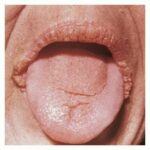

Clinically, acanthosis nigricans presents as brown to gray-black papillomatous cutaneous thickening in the flexural areas, including the posterolateral neck, axillae, groin, and abdominal folds. The distribution is usually symmetric. The affected skin has a dirty, velvety texture. In some cases, oral, esophageal, pharyngeal, laryngeal, conjunctival, and anogenital mucosal surfaces may be involved. In general, however, the back of the neck is the most consistently and severely affected area. The development of superimposed acrochordons in involved areas is well described . In particularly florid cases, involvement on the back of the hands over the knuckles and even on the palms can be seen. When the palms are involved, the rugated appearance of

the palmar surface has been called tripe palms and is usually associated with acanthosis nigricans seen in the setting of malignancy . In the majority of cases, the most important factor in diagnosing acanthosis nigricans is recognizing the usually associated hyperinsulinemia, which is a known risk factor for type 2 diabetes.